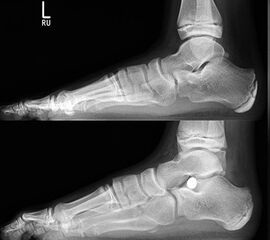

Röntgenkontrolle d.p. und seitlich unter Belastung nach 2, 6 und 12 Wochen und Beurteilung des Ergebnisses im Vergleich mit den präoperativen Bildern.

• Röntgenkontrolle d.p. und seitlich unter Belastung nach 2, 6 und 12 Wochen und Beurteilung des Ergebnisses im Vergleich mit den präoperativen Bildern (Abb.15).

Radiologische Beurteilungsparameter sind im belasteten seitlichen Strahlengang der Talo-Metatarsale-I-Winkel (Meary`s angle), der Calcaneusneigungswinkel (Calcaneus pitch), der Talusneigungswinkel, der Costa-Bartani-Winkel und der Talo-calcaneare Winkel. In der d.p.-Belastungsaufnahme der talo-calcaneare Winkel (Kite angle), der talo-metatarsale Winkel und der talonaviculare Überdachungswinkel 191432056781918 (De Pellegrin 2007, Schröder 2006, Hamel 2010, Arnold 2010). Hamel bietet mit seinem additiven TMT-Index eine radiologische, quantifizierbare Vergleichsmöglichkeit bei dreidimensionaler Erfassung der Fehlstellung (Hamel 2006, Hamel 2010, Kuhn H 2010, Arnold 2010).